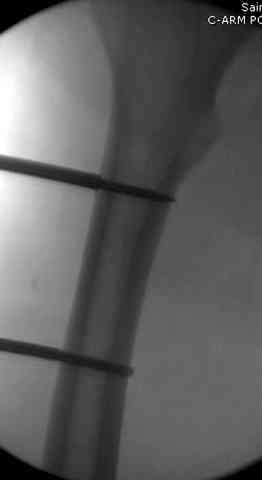

здесь случай с политравмой, перелом зафиксирован наружным фиксатором, после третьей irrigation&debridment фиксация бедра пластиной с последующей кожной пластикой.